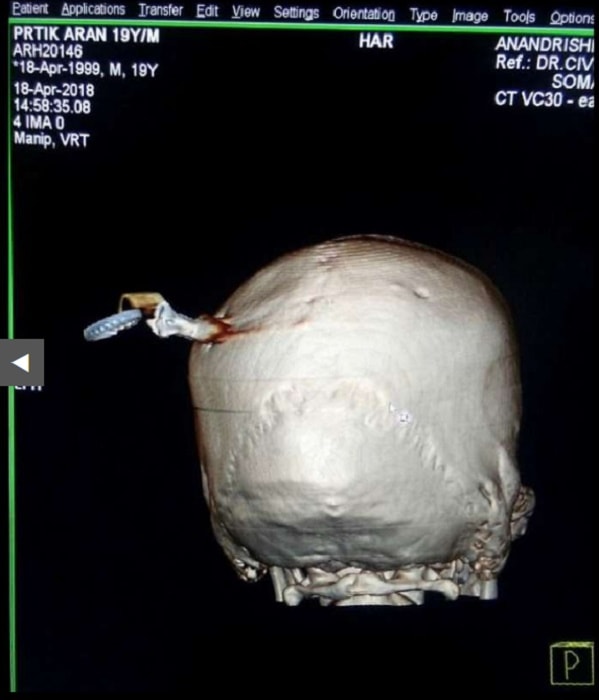

GHODEGAON – Un 19enne originario dello Stato indiano del Maharashtra è stato sottoposto ad un delicatissimo intervento chirurgico dopo che gli è finita conficcata in testa una chiave da moto, che se si fosse posizionata pochi centimetri più in là lo avrebbe ucciso.

Il giovane ha subìto il terribile infortunio durante una rissa nel villaggio di Ghodegaon nel distretto di Ahmednagar. È stato dimesso tre giorni dopo l’incidente e pare si stia riprendendo.

“Questa settimana è previsto un controllo di routine, ma le sue condizioni fanno ben sperare”. Le immagini rilanciate da Dagospia sono molto forti e mostrano chiaramente le chiavi conficcate nel cranio.